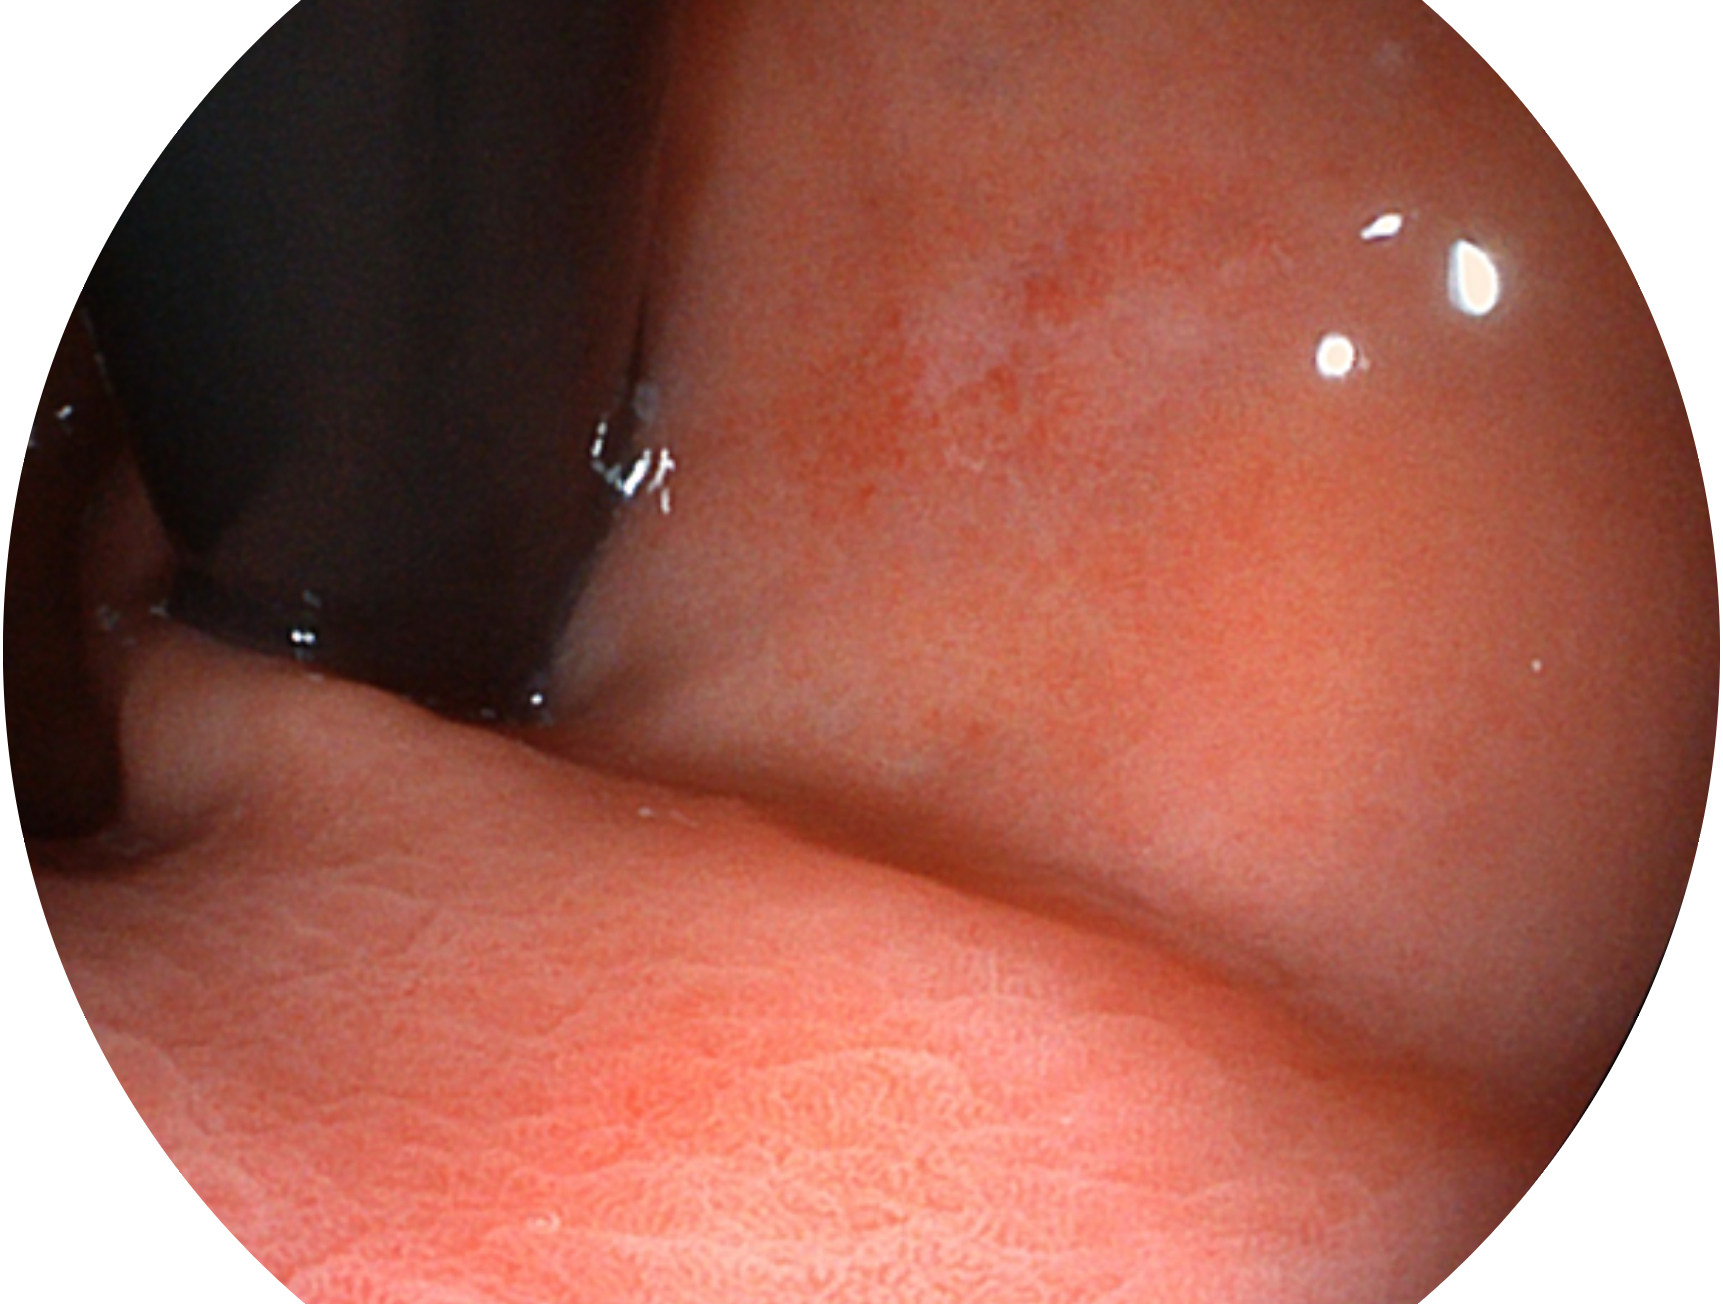

百老汇电子游戏官网新开发的内镜染色技术,主要是基于多波长LED 光源的开发,VLS-55Q 四波长LED 光源是由四个不同颜色的LED光按照相应照明模式所规定的特定发光比例进行合束后形成,合束后形成的照明光的光谱由红光、绿光、蓝光及蓝紫光这四个不同的波段范围构成。具有更高光谱自由度,通过光谱比例的控制,实现了聚谱成像技术,英文全称为“Spectral Focused Imaging, SFI”,缩写为“SFI”和光电复合染色成像技术,英文全称为“Versatile Intelligent Staining Technology, VIST”,缩写为“VIST”。